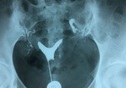

弓形子宫是由于孕期缺乏某种物质,从而导致的一种先天性的发育畸形情况,是子宫底部发生凹陷,从而使子宫腔的形状发生改变,这种疾病会对怀孕有一定的影响,不仅会降低受孕几率,还有可能会造成流产,如果一般情况下,一般是不需要治疗的,但如果出现了多次流产、不孕等症状,就应该及时进行子宫融合术。 弓形子宫什么意思弓形子宫,也叫做鞍状子宫,一般不会表现出较为明显的临床症状,也不会对月经周期产生什么影响,但弓形子宫这种疾病很多女性都不是很了解,因此大家可以了解一下弓形子宫的相关知识。定义弓形子宫是一种子宫畸形的情况,这是一种宫底部发育不良,宫底中间凹陷,宫壁会略微凸向宫腔,双侧苗勒管在中线没有完全靠拢,也就是宫底底部融合不全,最早导致子宫顶部是轻度凹陷,并表现出鞍状,但宫体和子宫颈正常。因为孕期缺乏某种物质,就会导致发育出现异常情况,弓形子宫不会对患者造成伤害,也没有明显的临床症状,所以孕前是不会检查出来的,有些宝宝直到生出来才被检查出是弓形子宫,这会导致女性出现难怀孕、易流产的症状。弓形子宫引起原因弓形子宫的引起原因是十分复杂的,目前医学界对于这种疾病并没有太大的了解,只知道这是一种先天性的子宫畸形疾病,可能是孕妇在妊娠期间缺乏某种物质,从而导致胎儿的子宫发育不良,最终出现弓形子宫。 弓形子宫一般很难在孕期被检查出来,因为不会出现明显症状,但患者会在出生后被诊断出来,并影响胎儿将来的生育能力,由于弓形子宫的病因还未可知,所以也没有什么预防措施。弓形子宫如何治疗除了对生育能力的影响之外,弓形子宫对女性没有多大影响,可以通过阴道四维彩超和电子立体宫腹腔镜检查等来诊断病情,在确诊之后,弓形子宫如果比较严重,就需要采取一些干预治疗措施:内分泌治疗:部分患者可以通过内分泌情况,服用调节内分泌药物,不过这个办法并不是对于所有患者都有疗效,对于大部分的患者来说,内分泌治疗法是没有太大效果的;子宫融合术:如果弓形子宫患者已经导致反复流产了,就需要尽快进行治疗,把两个分开的子宫角,从一侧宫角至对侧宫角作一横切口,对半切开肌壁,将两旁切口面对缝一起;宫腔镜治疗:宫腔镜手术能够治疗很多的妇科疾病,弓形子宫也不例外,通过宫腔镜手术能够治疗一些症状较轻的弓形子宫情况,切除一些隆起的纵隔情况。 如果弓形子宫的症状较重,就可以采取以上这些治疗办法进行治疗,如果患者症状较轻,或者女性没有备孕计划,因为这种疾病对于女性的身体没有明显影响,就无须接受特别的治疗。弓形子宫治疗费用一般来说,弓形子宫属于一种子宫畸形情况,而对于子宫的整形手术治疗费用在5000-5000元左右,但具体的治疗费用是不确定的,根据医院的等级和所处城市而言,费用是有一定差异的。弓形子宫都是通过矫正手术进行治疗的,但治疗手术有不少的选择,每项手术涉及到的费用也是不一样的,对于一些症状较轻不影响怀孕的女性来说,就可以不用手术,也不用进行特殊治疗,所以不同患者的治疗费用差异很大。弓形子宫如何怀孕弓形子宫并不一定导致患者不孕,部分患病较轻的女性是可以正常生育的,但是还有一些患者因为弓形子宫的缘故,已经出现了多次流产、胎停的情况,可以通过以下这些办法怀孕:自然怀孕:部分还有生育能力的患者,在经过手术治疗之后,术后一段时间后,前往医院复查,确定已经恢复正常生育能力,就可以安排同房了,然后就有几率自然怀孕了;人工授精:如果弓形子宫患者无法自然怀孕,就可以先进行人工授精的治疗,患者通过人工授精是有机会怀孕的,但人授的怀孕几率是比较低的,往往需要多次进行;试管婴儿:如果弓形子宫患者也是可以进行试管婴儿治疗的,医生可以通过医学挑选质量更好的卵子和精子,然后提高胚胎的发育潜力,降低弓形子宫导致流产的几率。 总的来说,弓形子宫也是有机会怀孕的,患者可以根据医生的指导意见来选择合适的方式来怀孕,怀孕之后要按时进行孕检,放平心态,及时了解胎儿的发育情况。